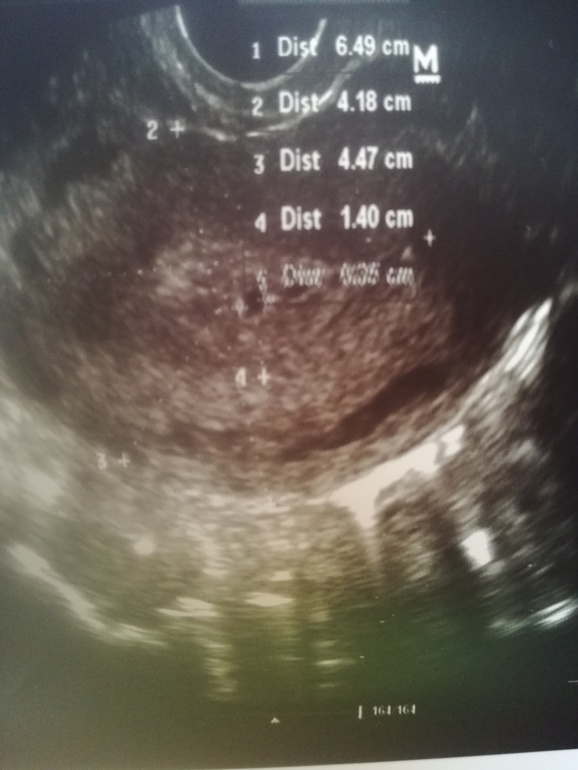

Сделала УЗИ. 18дпо, 30дц. Вчера хгч был 935. Пя 0,36см прикрепился на дне матки. Эндометрий на 7дпо был 8 мм, сегодня 14 мм, пышный. Матка 65*41*45 миометрий однородный. Жт в левом яичнике, сказала что он как будто воевал.шейка матки 40, однородный. Цервикальный канал сомкнут. Па в щадящем режиме. Рядом с пя будто ещё что-то есть. Сначала предположила что второй формируется, но дф был то один. Через 2 недели повторить.

На первом фото, прям где цифра 1 стоит. )

Но на фото этих может и не видно ничего, а в процессе узи они бывает всего на пол-миллиметра руку сдвинут с места, а картинка поменялась радикально. ))

Есть там пятнышко, но таких пятнышек много там))). Даже справа в виде сердечка))). Я в УЗИ ничего не понимаю. Когда ей сказала, что был 1 фолликул она усомнилась в своём предположении.